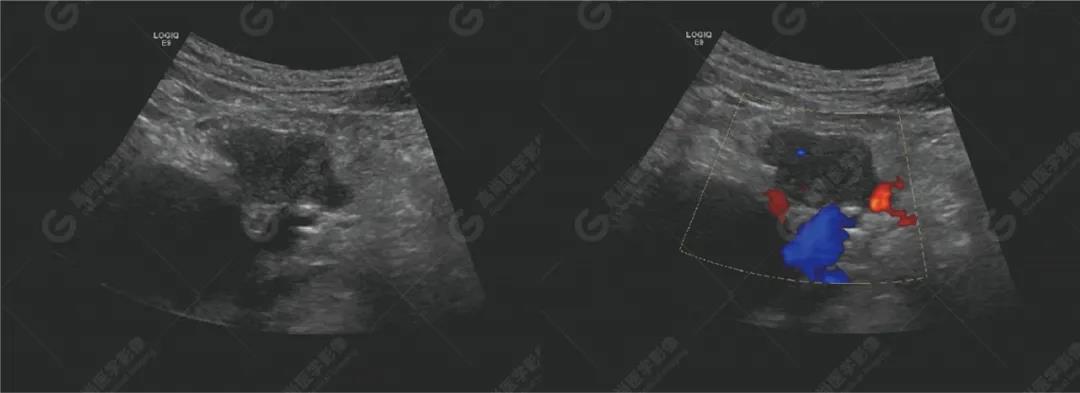

超聲檢查

超聲檢查所見:胰腺形態(tài)不規(guī)則,胰頭探及兩個實(shí)性低回聲團(tuán),大小分別約48mm×22mm、30mm×23mm,邊界不清,形態(tài)不規(guī)則,內(nèi)回聲欠均勻,CDFI顯示內(nèi)部可見少許血流信號。主胰管無擴(kuò)張。

腹膜后可見數(shù)個低回聲,較大約25mm×13mm,邊界清,形態(tài)不規(guī)則,部分相互融合,CDFI顯示其內(nèi)可見點(diǎn)狀血流信號。